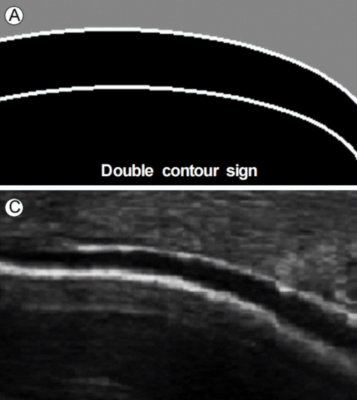

Siêu âm có khả năng chẩn đoán gout không xâm lấn nhờ phát hiện tinh thể urat lắng đọng trên bề mặt sụn khớp (double contour sign, dấu viền đôi), các dạng lắng đọng tinh thể urat (tophaceous materials) và khuyết xương điển hình (typical erosion).